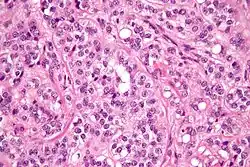

| Micrograph of a Sertoli–Leydig cell tumour. The Leydig cells have abundant eosinophilic or light pink cytoplasm. The Sertoli cells have a pale/clear cytoplasm. H&E stain. | |

The tumour is subdivided into many different subtypes. The most typical is composed of tubules lined by Sertoli cells and interstitial clusters of Leydig cells.